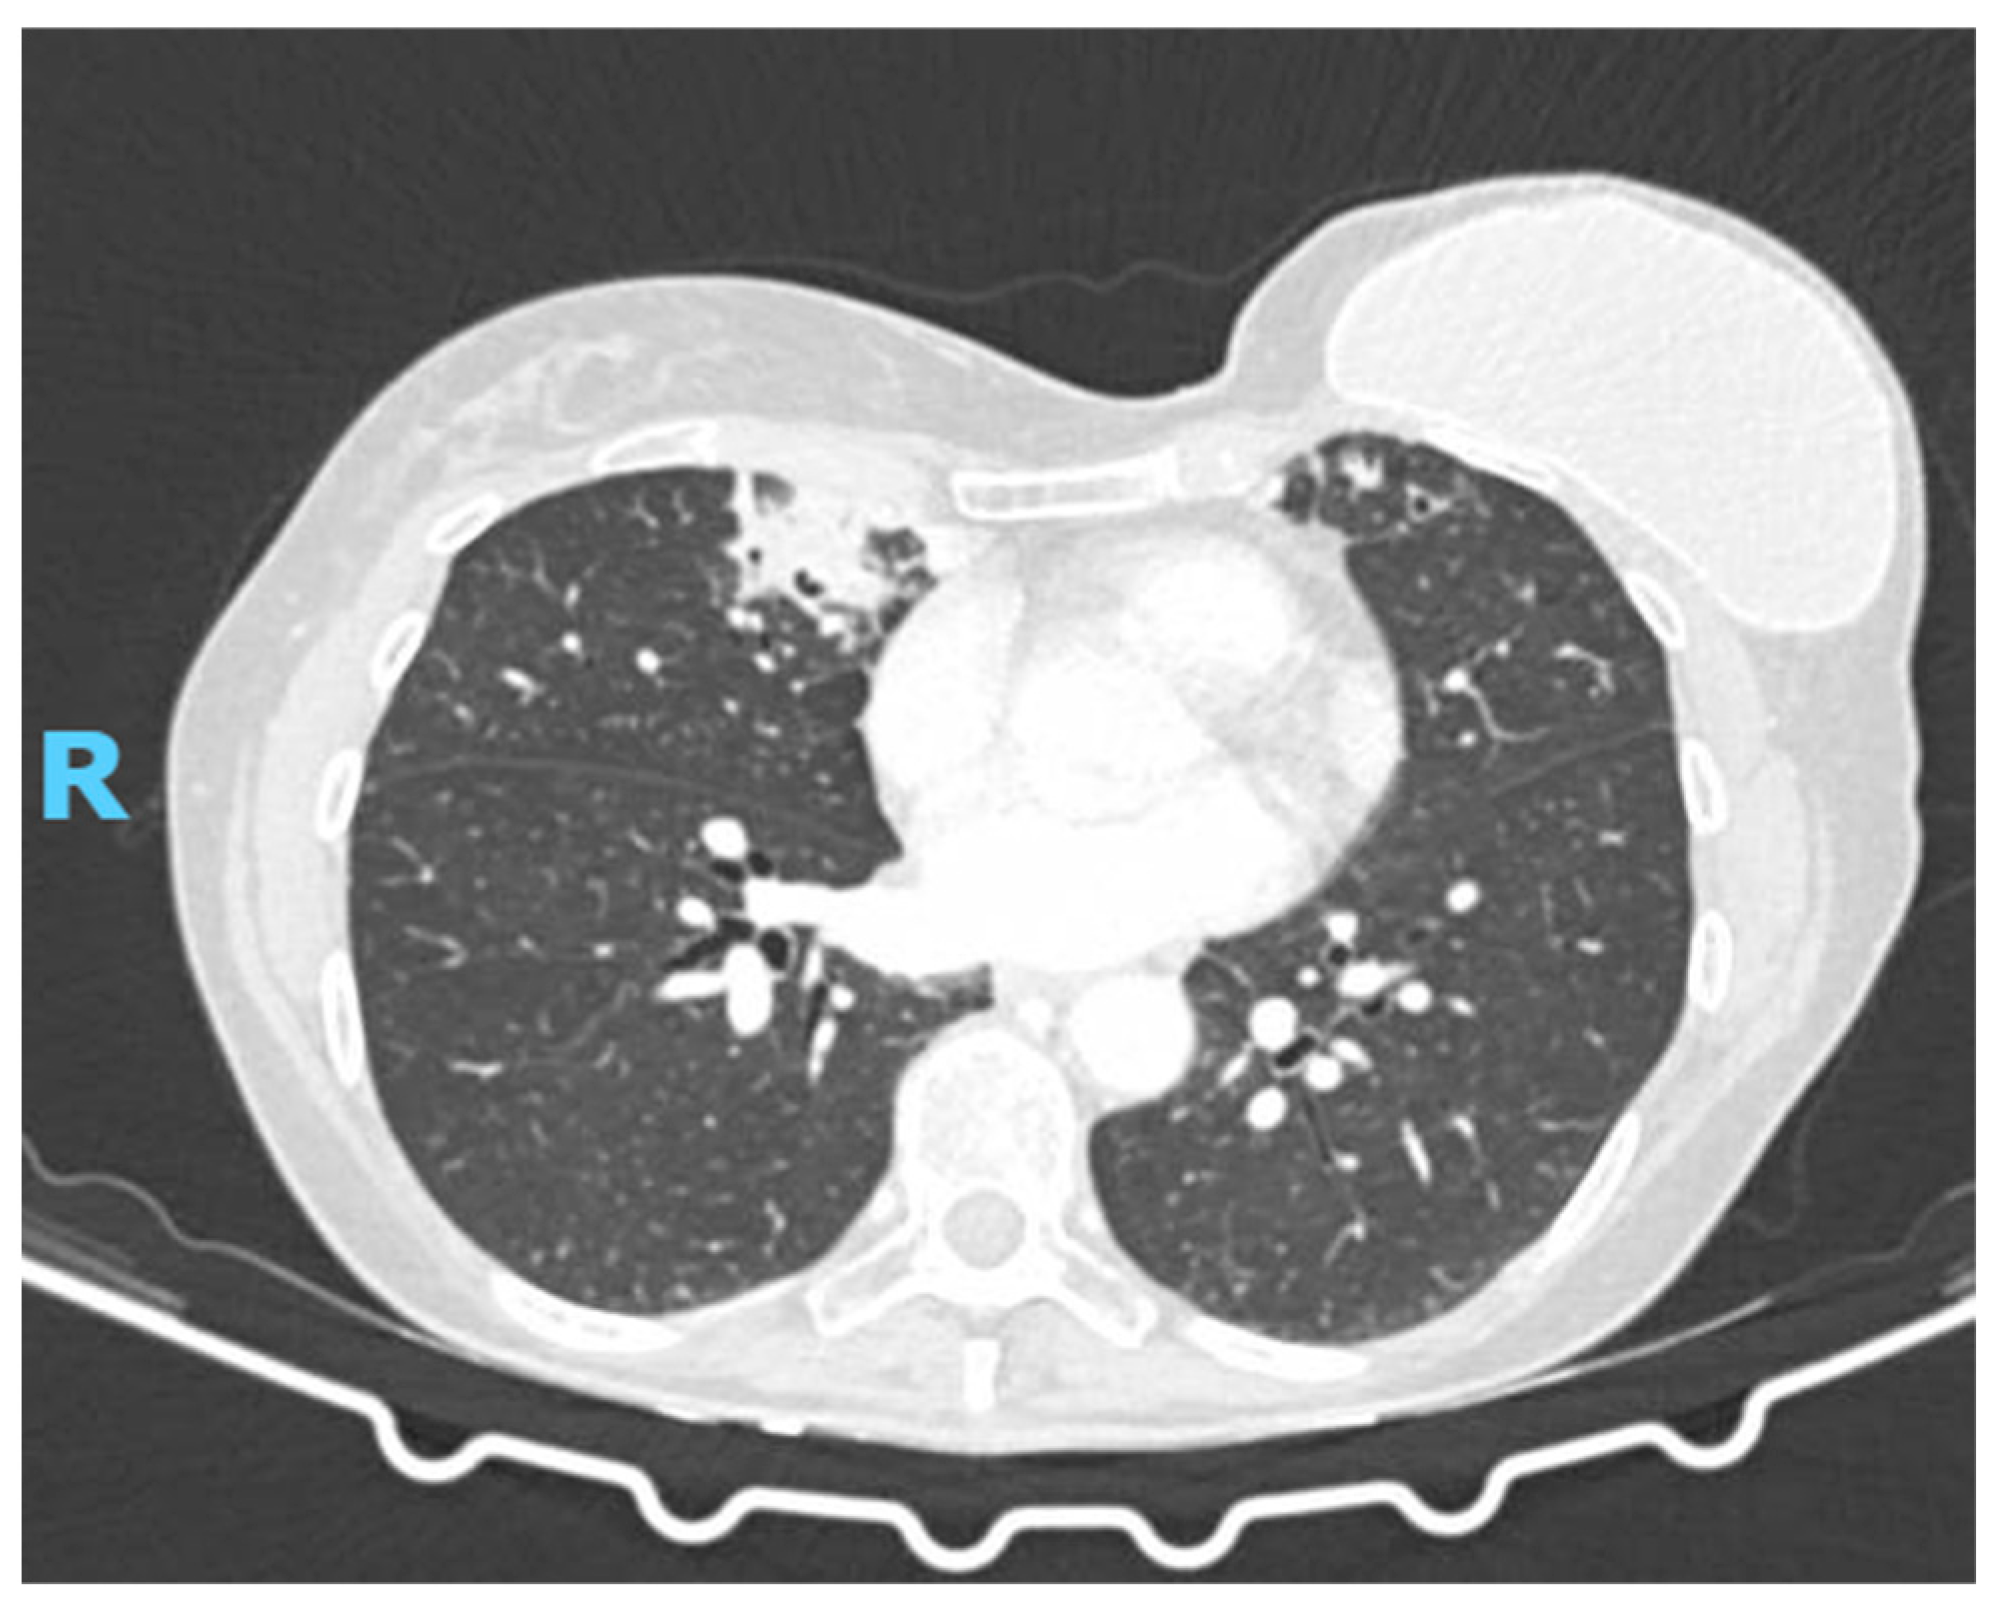

2. Case Presentation

2.2. Diagnostic Studies